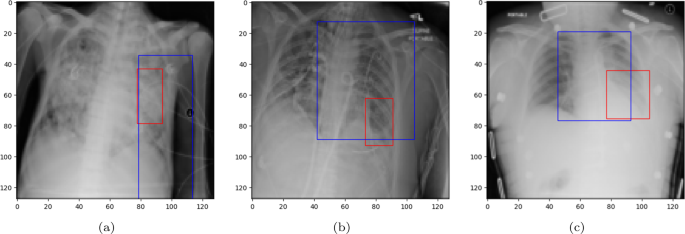

A bounding box (BBOX) is a rectangular region that is commonly used to localize (highlight) the interest area. Figure 8 illustrates the BBOX of some pneumonia disease instances predicted by the proposed ECGL model. The red box refers to the ground truth BBOX stated for the X-ray image, and the blue box demonstrates the predicted box by the ECGL model. It is important to note that the Base model cannot generate BBOX due to the lack of explanation constraints required for BBOX prediction.

Ground truth (red) and predicted (blue) BBOX regions in X-ray images: (a) and (b) represent the samples where the model predicts an incorrect label, while (c) corresponds to the case of the correct prediction

Looking at Fig. 8(a) and 8(b), it is evident that the proposed ECGL correctly predicted the BBOX, aligning with the true box, even though the model estimated a larger area. This points out that considering the BBOX constraints in the model as integrated explanation constraints is effective in highlighting the attention to more relevant regions. Figure 8(c) presents a case where the predicted BBOX is partially within the lung area and may highlight the need for more refined BBOX constraints to better capture the spatial extent of pneumonia.